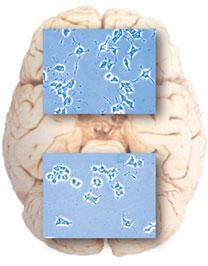

Dr Virginie Fontaine-Lenoir : Nos études ont permis de mettre en évidence que la prégnénolone avait un effet positif sur les neurones en se fixant sur le récepteur MAP2. Elle favorise la connexion neuronale. En fait, pour fonctionner correctement et surtout pour pouvoir communiquer entre eux, les neurones doivent créer des connexions grâce à des longs prolongements de leur paroi cellulaire. Ces fins prolongements que l'on appelle neurites sont constitués de microtubules. Les microtubules sont de très longues chaînes qui sont, un peu comme des « Legos », un assemblage de petites particules de tubulines. Ces microtubules constituent le squelette des prolongements neuronaux. Il faut comprendre que ces connexions entre les neurones ne sont pas statiques, les connexions se font et se défont, et ainsi les microtubules ont la faculté de pouvoir faire grandir ou diminuer les prolongements neuronaux afin de créer de nouvelles connexions. Nous avons vu par des études de cultures cellulaires sur des neurones que la prégnénolone favorisait l'allongement et la stabilité de ces prolongements neuronaux (Figure 1). Nous avons par la suite confirmé que la prégnénolone avait besoin de se fixer sur le récepteur MAP2 que nous avons identifié pour permettre ce mécanisme. Ce fut une belle découverte car c'était la première preuve que la prégnénolone agissait par MAP2 au niveau du système nerveux pour favoriser la croissance des neurites et leur résistance.

La prégnénolone protège-t-elle nos neurones ?  Dr Virginie Fontaine-Lenoir : Oui, la prégnénolone favorise la résistance des neurites, donc des neurones. Nous avons réalisé plusieurs études avec une drogue, le nocodazole. Cette molécule empêche l'allongement des microtubules et entraîne ainsi indirectement leur raccourcissement. Nous avons observé que l'ajout de prégnénolone contrecarrait l'effet de la drogue. L'effet négatif de raccourcissement provoqué par le nocodazole est ralenti grâce à la prégnénolone. Les prolongements des neurones résistent donc mieux à l'agression de la drogue quand nous les supplémentons en prégnénolone. Donc nous avons pu conclure que la prégnénolone a bien un effet protecteur au niveau des neurones.

Dr Virginie Fontaine-Lenoir : Oui, la prégnénolone favorise la résistance des neurites, donc des neurones. Nous avons réalisé plusieurs études avec une drogue, le nocodazole. Cette molécule empêche l'allongement des microtubules et entraîne ainsi indirectement leur raccourcissement. Nous avons observé que l'ajout de prégnénolone contrecarrait l'effet de la drogue. L'effet négatif de raccourcissement provoqué par le nocodazole est ralenti grâce à la prégnénolone. Les prolongements des neurones résistent donc mieux à l'agression de la drogue quand nous les supplémentons en prégnénolone. Donc nous avons pu conclure que la prégnénolone a bien un effet protecteur au niveau des neurones.

Dr Virginie Fontaine-Lenoir : Oui, cela est fort probable. Il faut savoir que de nombreuses maladies neurodégénératives s'expliquent par la destruction des microtubules des neurones et de leurs neurites. Cela entraîne une mauvaise connexion entre les neurones. Le bon fonctionnement de notre réflexion et de notre mémoire n'est possible que si la connexion entre nos neurones est correcte. Notre découverte laisse entrevoir de nombreuses possibilités thérapeutiques pour l'homme, notamment pour lutter contre la maladie d'Alzheimer et des traumatismes de la moelle épinière. Ces événements entraînent la désorganisation du cytosquelette (constitué de microtubules) des neurones et la mort cellulaire. Nous sommes convaincus qu'à l'avenir, la prégnénolone pourra être utilisée dans ces pathologies neurodégénératives pour protéger les microtubules des neurones et stabiliser les neurites. Nous commençons à étudier l'effet de « neuroprotection » et de la réparation neuronale de la prégnénolone sur des animaux qui reproduisent des pathologies neurodégénératives humaines et nos résultats sont pour l'instant prometteurs. Une étude préclinique est en cours et teste un dérivé synthétique de la prégnénolone. Ce composé a des effets positifs après un traumatisme de la moelle épinière chez le rat. Nous espérons que nos recherches aboutiront au développement clinique de nouveaux traitements préventifs et curatifs pour des maladies neurodégénératives.